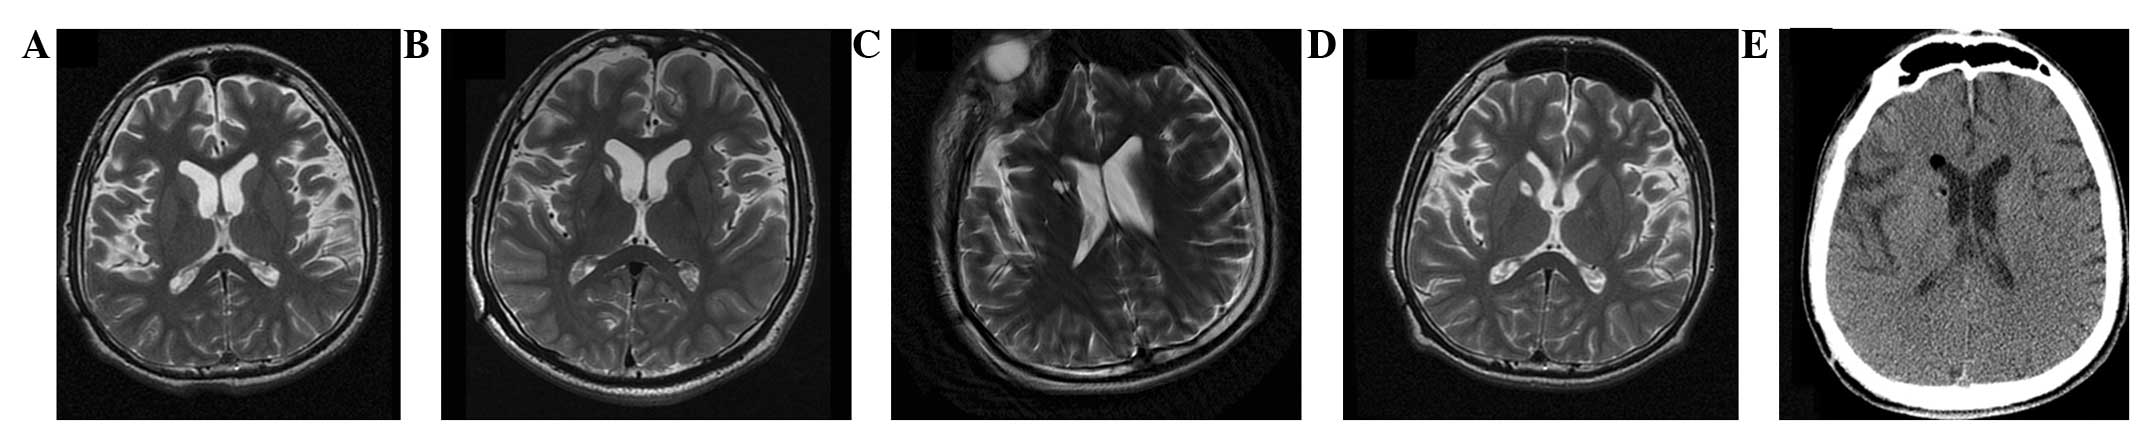

本研究選擇的患者為18歲男性,患有PTD,預產期剖宮產出生,無任何遺傳病家族史,無腦炎、黃疸、腦腫瘤病史或外傷。他在5歲時首次出現(xiàn)左下肢不自主痙攣和扭轉,沒有任何誘發(fā)因素。臨床特征從5歲至9歲逐漸擴展到全身。18歲時,患者無法書寫、抓握、站立或行走。他吞咽固體食物有些困難,但沒有癲癇癥狀。患者智力正常。頭部計算機斷層掃描(CT;圖1a)和磁共振成像(MRI;圖2a)提示大腦輕度萎縮。PTD是根據(jù)上述數(shù)據(jù)診斷的。

(A) 術前CT顯示腦萎縮。

(BE)術后1年、2年、3年、4年CT與術前相比均無明顯變化。

(A) 術前 MRI 顯示腦萎縮。 (BD)術后1年、3年、4年MRI與術前MRI相比無明顯變化。 (E) 術后3天,計算機斷層掃描顯示沒有出血或水腫。

遺傳分析發(fā)現(xiàn)患者DYT1 ( TOR1A )第五外顯子存在突變 (907-909 delGAG) 。他對神經外科手術表現(xiàn)出良好的耐受性,并于4點出院。沒有與細胞植入或外科手術相關的嚴重不良事件。POD時的CT掃描顯示沒有出血或水腫(圖2e)。術后1個月,患者的PTD癥狀開始改善。BFMDMS逐漸增加,從術前的21分別增加到術后1、2、3和4年的18、17、15和13,術后4年改善38.1%(表1)。

CT(圖1b-e)和MRI(圖2b-d)掃描顯示4年隨訪期間沒有顯著變化。 手術前1天(圖1f)和手術后1、2、3和4年(圖1g-j) 獲得18F-FDGPET掃描。術后雙側植入部位豆狀核和丘腦18F-FDG攝取值較術前增加。這一結果表明,自移植以來,葡萄糖代謝逐年略有增加。